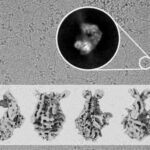

Un team di ricerca ha ora identificato più siti sulla proteina Spike di SARS-CoV-2 che possono aiutare a spiegare come mutazioni specifiche rendano le varianti emergenti più infettive e potrebbero anche essere utilizzate come bersagli aggiuntivi per l’intervento terapeutico. “Sono in corso ricerche significative per esaminare come il dominio di legame del recettore (RBD) sulla punta della proteina Spike a forma di clava si attacca a un recettore ACE2 su una cellula umana, ma poco si sa sugli altri cambiamenti che si verificano nella proteina Spike come risultato di questo attaccamento. Abbiamo scoperto “punti caldi” più in basso sulla proteina Spike che sono fondamentali per l’infezione da SARS-CoV-2 e potrebbero essere nuovi bersagli oltre RBD per l’intervento terapeutico”, spiega Ganesh Anand, Professore Associato di Chimica, Penn State.

L’HDXMS utilizza l’ossido di deuterio (D 2 O) o l’acqua pesante, un isotopo dell’acqua non radioattivo, presente in natura che si forma dal deuterio o dall’idrogeno pesante, come sonda per tracciare le proteine. In tal caso, i ricercatori hanno posizionato i recettori ACE2 e la proteina Spike in acqua pesante e hanno acquisito le impronte ACE2 sulla proteina Spike. “Se metti la proteina Spike e il recettore ACE2 in una soluzione realizzata con D2O, le superfici e le regioni più flosce su entrambe le proteine scambieranno più prontamente gli idrogeni con il deuterio, rispetto ai loro interni. E le impronte di ciascuna proteina sul partner di legame possono essere facilmente identificate dalle aree in cui si vede poco deuterio e si rileva solo l’idrogeno normale”, dice Ganesh Anand, Professore Associato di Chimica, Penn State.

Con l’aiuto di questo metodo, i ricercatori hanno stabilito che il legame del recettore ACE2 e della proteina Spike è necessario per le proteasi simili alla furina, una classe di enzimi umani, che agiscono per tagliare la punta, nota come subunità S1, della Spike protein, che è il passaggio successivo nell’infezione da virus della cellula.

“Le proteine Spike sulla superficie del virus ruotano per cercare e attaccarsi al recettore ACE2 che può essere paragonato a una mano che tiene ciocche di capelli: i grappoli di proteine Spike. Legarsi a Spike lo stabilizza in modo che possa essere tagliato con le forbici della proteasi della furina. Dopo che le proteasi furiniche hanno tagliato la proteina, la parte che rimane, la subunità S2, è ciò che si fonde con le membrane della cellula, consentendo l’ingresso al virus nella cellula “, spiega Ganesh Anand, Professore Associato di Chimica, Penn State.